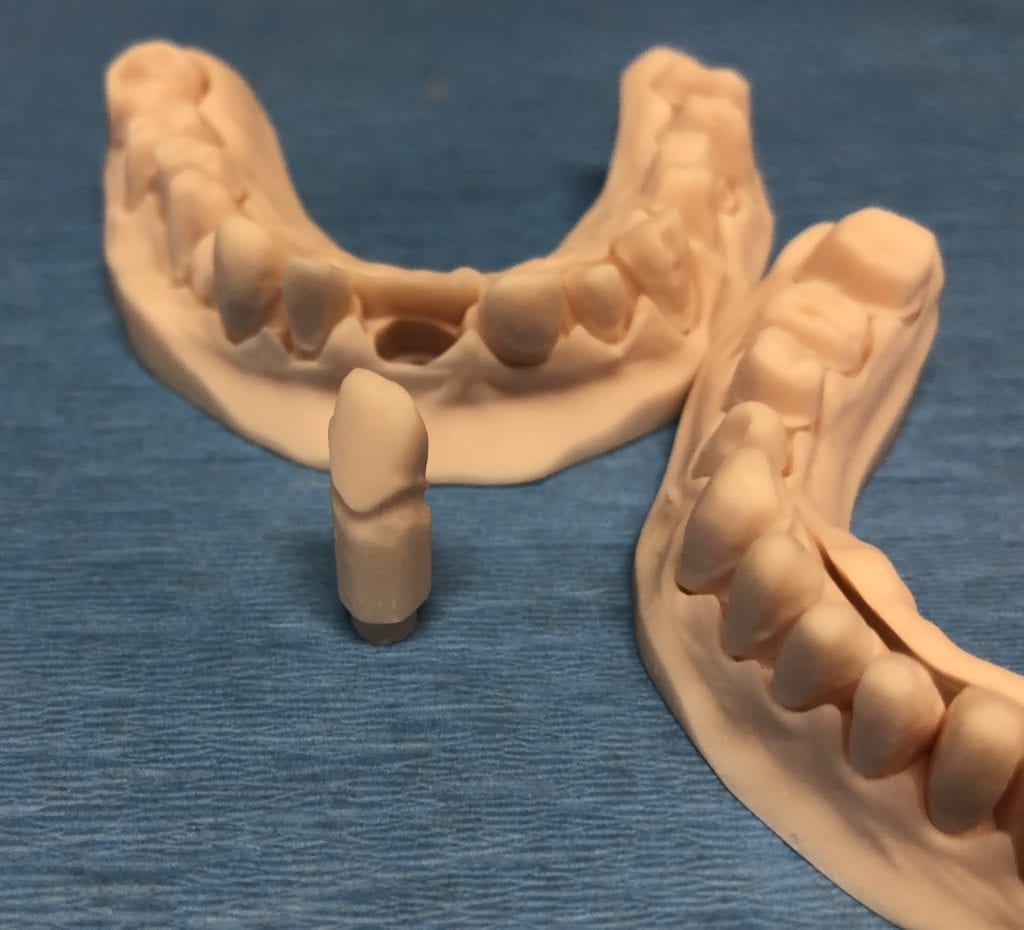

The case was designed by CADENT BESSA, and the models were printed by Burbank Dental Lab with Carbon Printers. There restorations were milled and cut back and layered by Burbank Dental Lab

IMAGES OF PRINTED MODELS